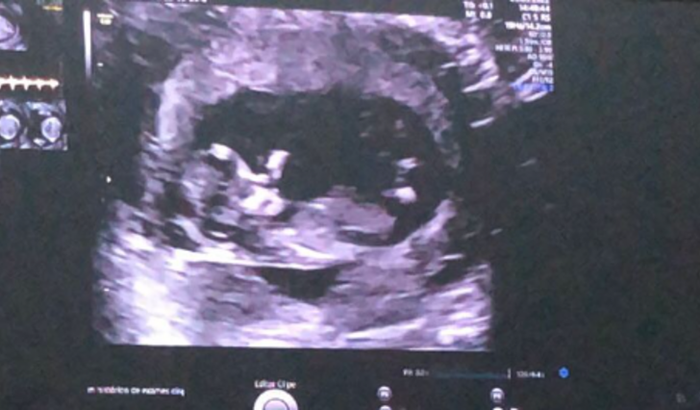

Olá eu me chamo Alessandra sou a mãe do Noah nosso 3 filho. Os nossos 2 primeiros filhos perdemos ainda antes de completar 3 meses de gestação. fomos embora para tentar fugir da dor, e vendemos tudo para irmos, não nos adaptamos ao novo pais e voltamos para Brasil, sem nada. Quando chegamos aqui descobrimos que estava a espera do nosso bebe milagre, pois ele veio logo após o ultimo aborto que tive em outro pais. Eu não posso trabalhar por isso as coisas estão pesadas para meu marido, ele trabalha para pagar as contas e comprar comida, as vezes tiramos da conta de casa para pagar os exames, e alguns remédios que preciso tomar. Criei essa vakinha com esperança de conseguir montar o quarto do nosso filho e pagar os últimos exames pois ja estou com 6 meses de Gravides. desde já agradeço Deus abençoe.